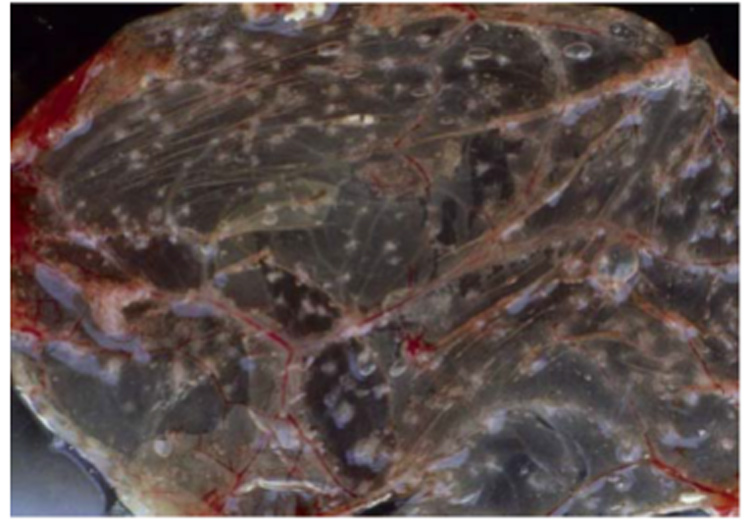

常用的病毒分離方法是將病料接種于雞胚的絨毛尿囊膜。傳喉病毒會在此處形成不透明的斑塊(圖4)。病毒分離相對于PCR成本更高,耗時更長,對采樣和送樣的要求也更高。但是通過病毒分離可以獲得活病毒,以便于做進一步的毒力和組織嗜性等方面的研究。PCR和病毒分離都存在一個相同的缺陷,即只能證明傳喉病毒在病雞體內(nèi)存在,但是不能直接證明是傳喉病毒導(dǎo)致了雞發(fā)病。

圖4:雞胚絨毛尿囊膜上的斑塊(來源:LDA 22)